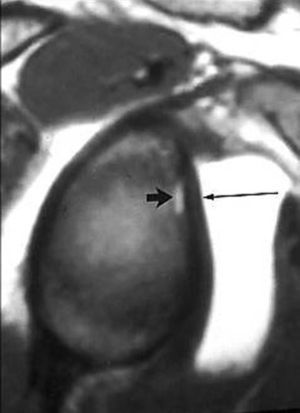

POLPSA (posterior labral periosteal sleeve avulsion)

Esta lesión se asemeja a la ALPSA, pero ocurre en el borde glenoideo posterior. El LG se halla desplazado hacia dentro y por detrás del borde glenoideo posterior. El mecanismo de producción del POLPSA es una dislocación posterior, y por tanto se puede encontrar también un Hill Sachs invertido19 (fig. 14).

. Artrorresonancia axial T1 con supresión grasa donde se observa una rotura del labio glenoideo posterior con desplazamiento posteromedial (flecha). Nótese la situación del labio glenoideo en comparación con una rotura sencilla, no desplazada, que se observa en la figura 13. Obsérvese la presencia de una lesión de Hill-Sachs invertida (cabezas de flecha), en relación con una dislocación posterior con reducción.Lesión de Bennett